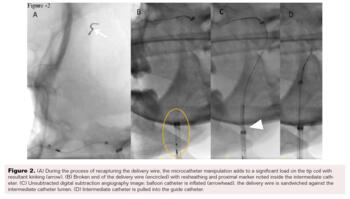

The cerebral angiogram revealed a large saccular aneurysm (measuring 4.2 mm at the neck, 1.3 cm at the dome, and 1.8 cm in length) in the supraclinoid left internal carotid artery (ICA). Because of the size and location of the aneurysm as well as the wide neck, endovascular FD placement was planned.

The Pipeline Flex embolization device (4.25 x 25 mm) was then deployed from the left supraclinoid ICA with an aim to jail the origin of ophthalmic artery, as per the plan (Figure 1). The check angiogram showed stasis within the aneurysm with preserved flow in the left ICA and its branches.